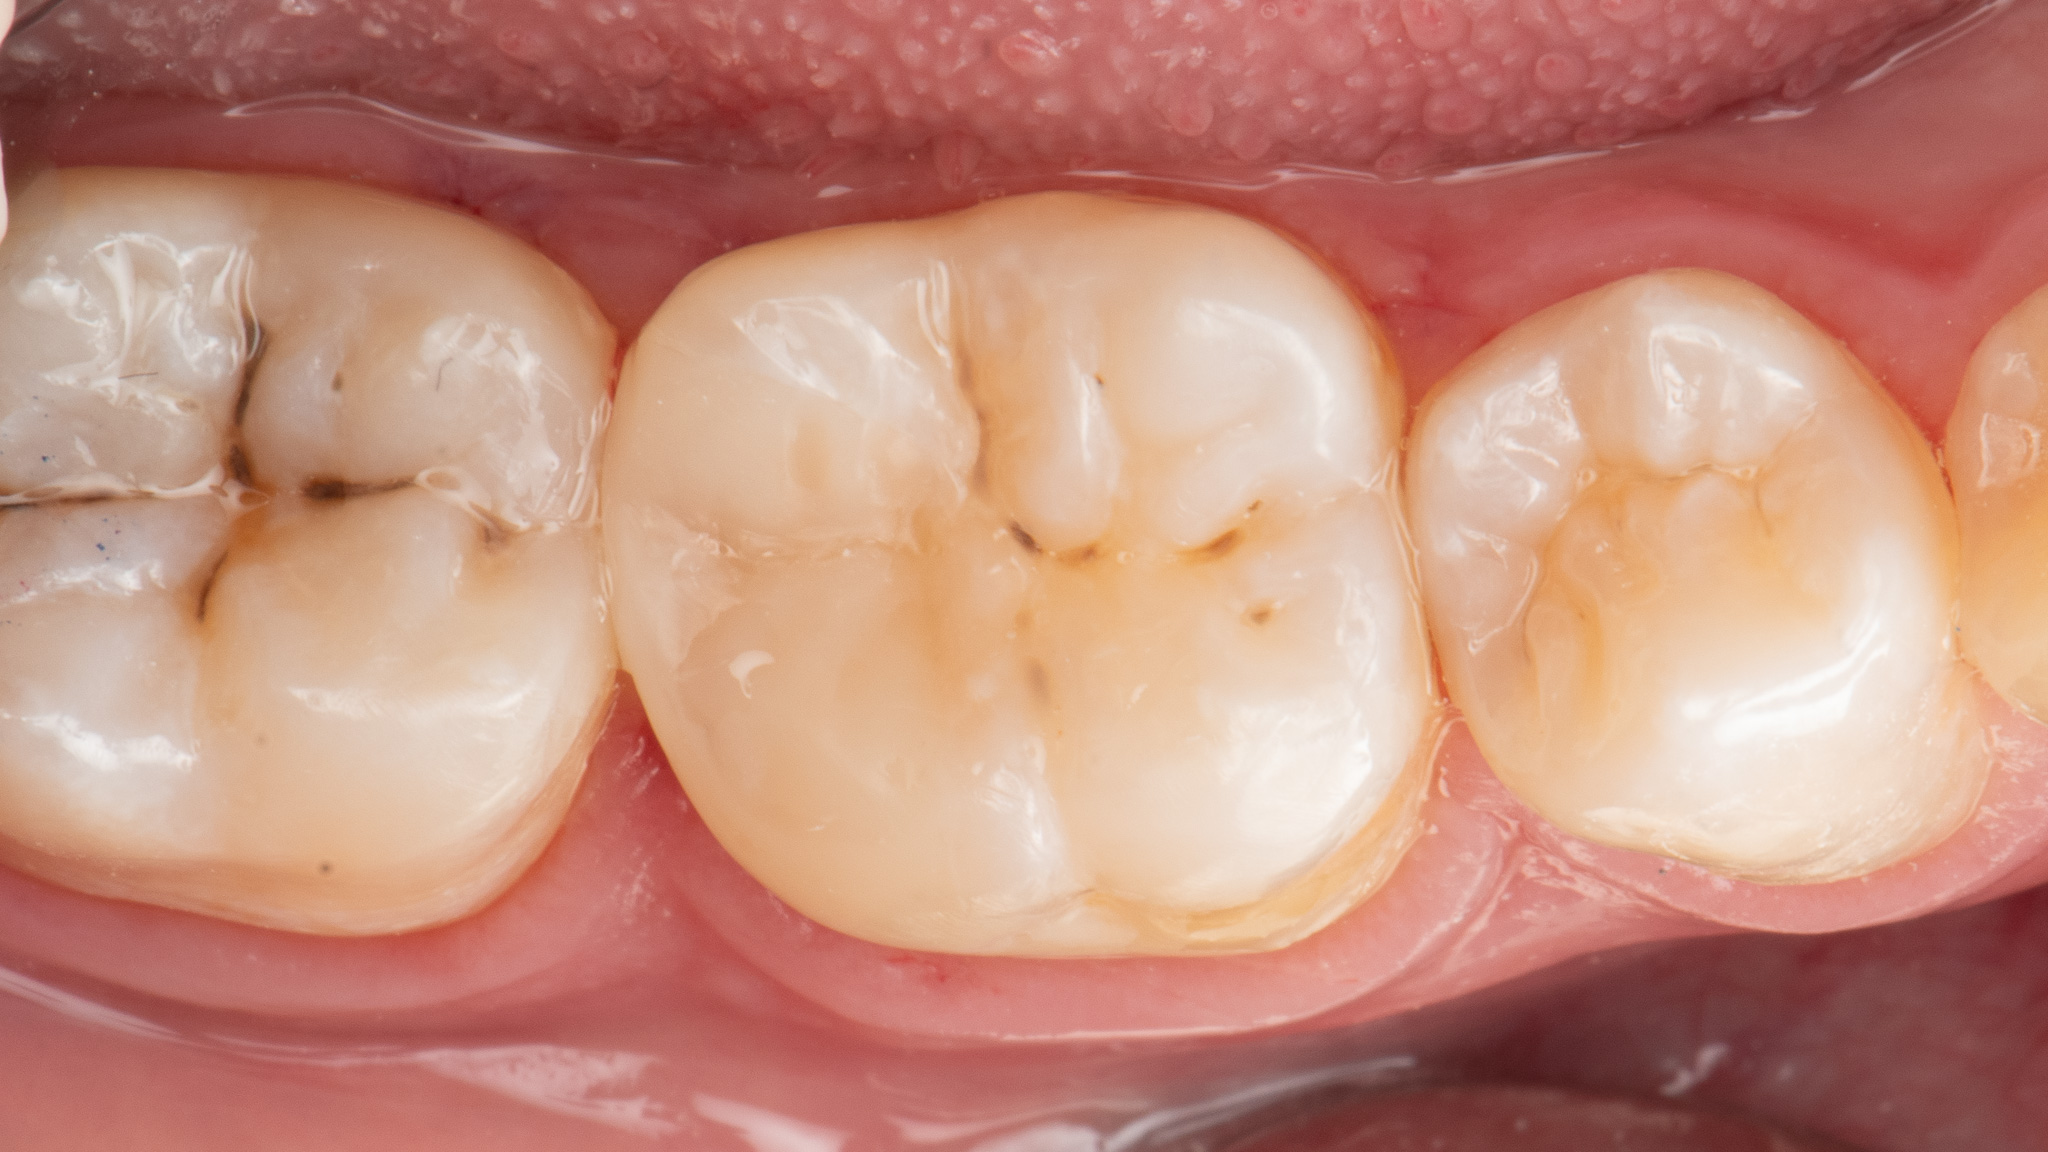

Pacjent 4

Leczenie próchnicy pierwotnej zębów bocznych (próchnica powierzchni stycznej zębów trzonowych która spowodowała odłamanie listwy brzeżnej) w zębie pierwszym trzonowym.

Odbudowa z odtworzeniem naturalnej morfologii zęba nowoczesnym materiałem światłoutwardzalnym 3M™ Filtek™ BulkFill One oraz Filtek Universal zapewniające nieporównywalną trwałość w czasie i odporność mechaniczną.

Leczenie zachowawcze odbywało się w osłonie koferdamu zapewniającej komfort pacjenta i suchość pola zabiegowego.